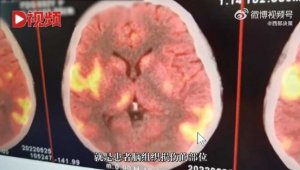

- 深圳女发烧一周没理 她昏迷2个月 医惊:脑部像被火烧(图)